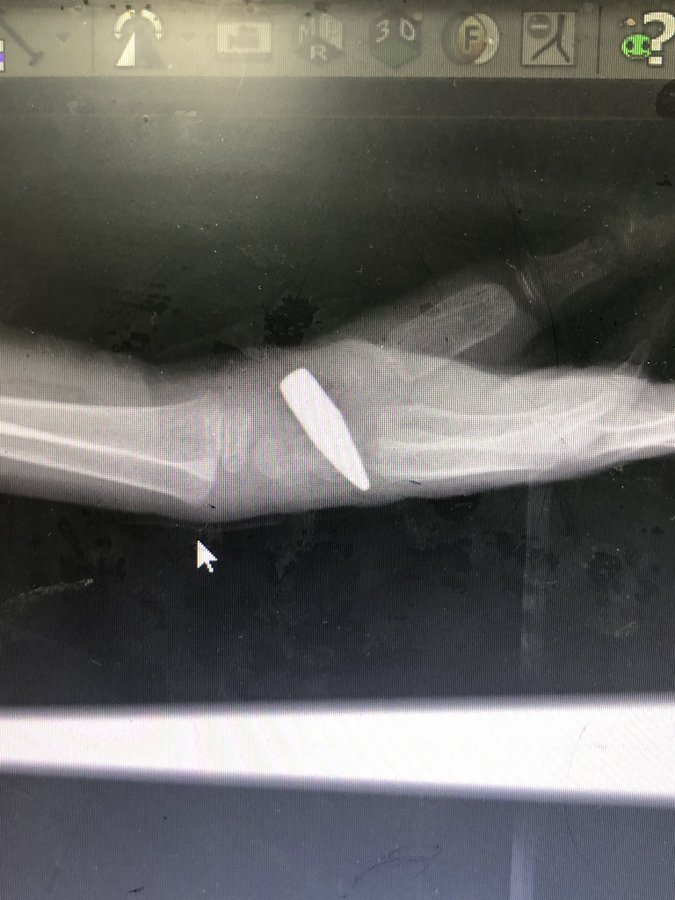

and I had the risk to get a bullet out of a 5 year old boy wrist in the emergency.

This gunshot was by airplane towards civilian around a UNRWA schools in the “safe area” of Middle area.